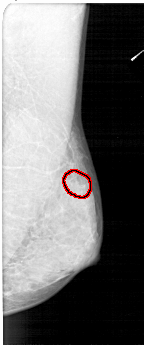

FILE: A_1352_1.RIGHT_CC.OVERLAY

TOTAL_ABNORMALITIES 1

ABNORMALITY 1

LESION_TYPE CALCIFICATION TYPE PLEOMORPHIC DISTRIBUTION CLUSTERED

ASSESSMENT 4

SUBTLETY 2

PATHOLOGY BENIGN

TOTAL_OUTLINES 1

BOUNDARY